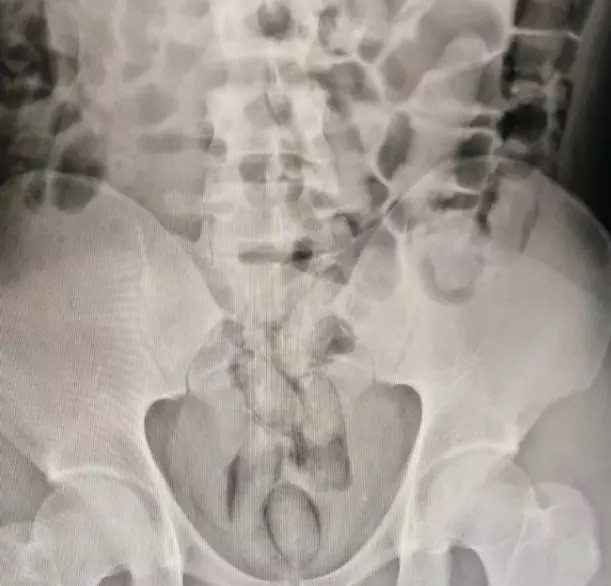

Um homem de 29 anos foi preso em flagrante com 29 cápsulas de drogas no estômago. O caso foi registrado pela Polícia Civil, na noite do domingo (18), em São Lourenço do Oeste, no Oeste de Santa Catarina.

O suspeito passou por exame de raio-x, que confirmou a existência das cápsulas com cocaína. Ele cumpria pena no presídio de Chapecó e estava em saída temporária de 7 dias. O caso segue sendo investigado pela Polícia Civil (PC).

29 cápsulas de drogas estavam no estômago do homem